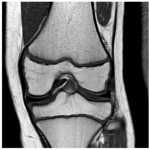

Menisco discoide medial: un cuadro infrecuente. Presentación de un caso y consideraciones sobre el tratamiento

Hugo Vasquez Diaz, Diego Toledo, Marco Gutierrez Gonzalez, Pedro Valdecantos